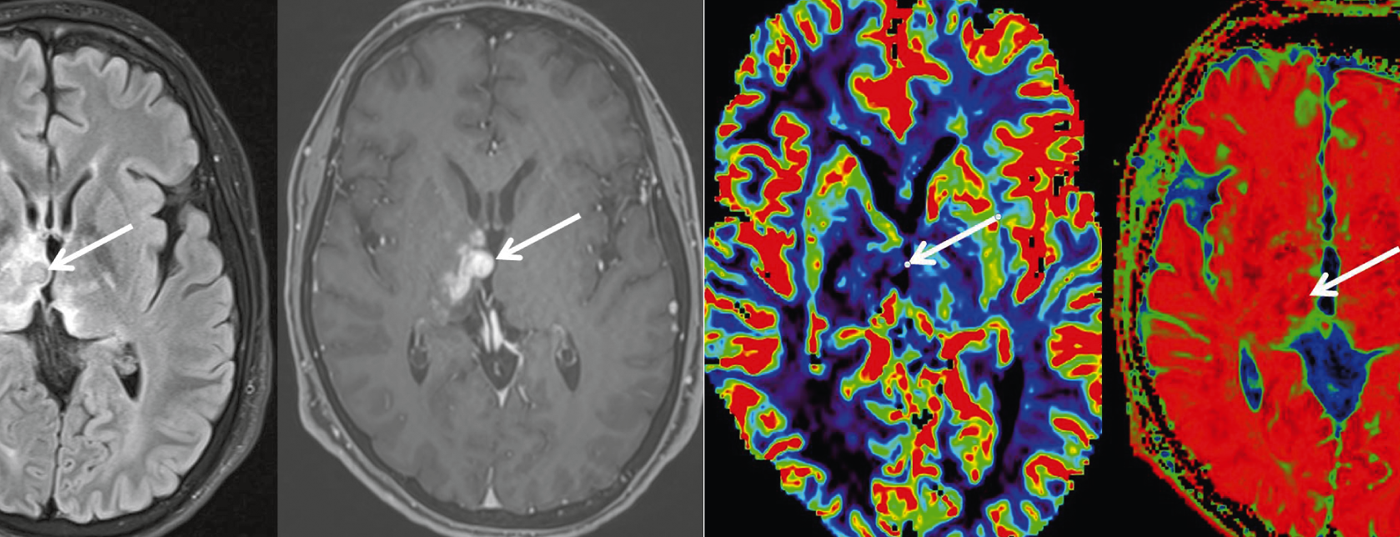

Erweiterte MRI-Diagnostik (Spektroskopie, DWI, PWI) und MRI-gestützte Biopsie

Einleitung: Primäre ZNS-Lymphome, überwiegend vom B-Zell-Typ, sind seltene Tumore mit einem Häufigkeitsgipfel im mittleren bis höheren Lebensalter. Die konventionelle MRT-Untersuchung liefert im Wesentlichen unspezifische Befunde einer zumeist KM-aufnehmenden, typischerweise Ventrikel-nahen Raumforderung. Der Wert der erweiterten MRT-Diagnostik und MRI-gestützten Biopsie wird im folgenden Fallbericht dargestellt.